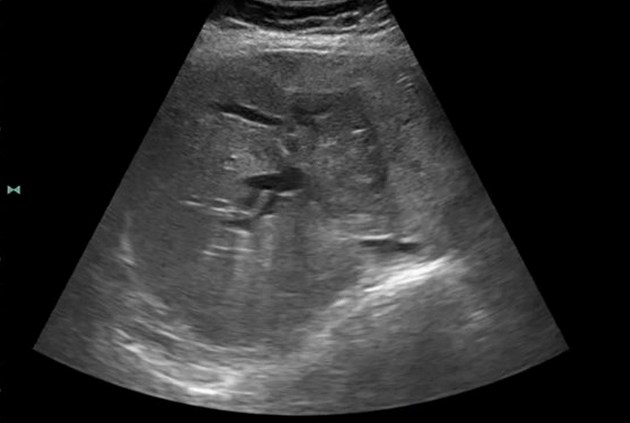

Ультразвуковое исследование печени

УЗИ — наиболее часто применяемый метод первичной диагностики заболеваний печени. Он позволяет получить объективное изображение структуры органа, выявить наличие новообразований, определить их размеры, форму и расположение. Новейшие ультразвуковые аппараты способны отличать доброкачественные образования от злокачественных, а также фиксировать признаки инвазии опухоли в окружающие ткани.

Одним из преимуществ УЗИ является его безопасность — этот метод не использует радиацию или ионизирующее излучение, что особенно важно при повторных исследованиях. Также важным аспектом является доступность: УЗИ можно делать практически в любой медицинской клинике или поликлинике, что позволяет проводить скрининг и мониторинг пациентов с высоким риском развития рака печени.

Ключевые признаки, которые выявляет УЗИ

| Признак | Описание |

|---|---|

| Образование в печени | Наличие однокамерных или многокамерных опухолей, их размер и структура |

| Кистозные образования | Легко отличимы от опухолей, но требуют дифференцировки |

| Контуры опухоли | Границы злокачественных образований часто неровные или размытые |

| Микроособенности | Отличие гипо- или гиперэхогенных включений, наличие кровотечений |

| Инвазия в сосуды | Рассмотрение изображений сосудистых структур и признаков их сдавления или проникновения опухолью |